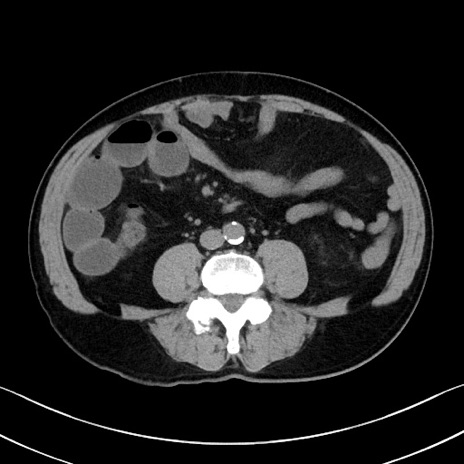

症例35(横断像)

【症例】70歳代 男性

【主訴】腹部膨満、嘔吐

【現病歴】昨日より腹部膨満感出現。本日増悪し、仙痛出現。嘔吐あり、受診。

【既往歴】糖尿病、胆摘後

【身体所見】BP 149/80mmHg、HR 74/min、BT 35.9℃、腹部:膨満、軟、圧痛なし。腸雑音減弱あり。上腹部正中切開瘢痕あり。

【データ】WBC 13500、CRP 1.72